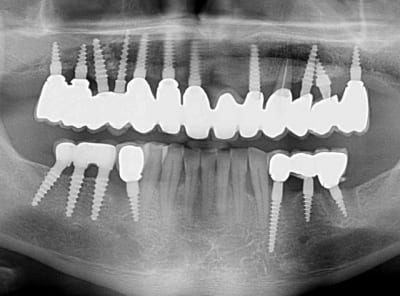

Bonjour flicflac je suis désolé de ma réponse tardive, oui il est vrai que ce n est pas beaucoup documenté ... je serai un menteur de dire que que je n ai jamais perdu des implants, surtout entre la 2eme et 8eme semaine après l implantation.Un échec vraiment à cause de la perte osseuse et avec le même process cela est arrivé une fois avec une madame, où l´os était encore infecté ( avant la chirurgie),mais après l ´échec (c était à la position 35) on a pu laisser le bridge. Malheureusement je n ai pas toutes les photos ici à Mallorque sur mon PC portable. Ci dessous une photo après 10 ans 46 47 et les implants au maxillaire.

Oui ca semble ....sur la opg radio tu peux voir la situation seulement deux semaines après l´implantation immédiate 34 jusqu´à 36 et 45, les derniers 2 photos montrent la même situation après un an ( où on a enlevé la supra construction pour un contrôle). Sur ce cas je voulais montrer la bonne régénération osseuse et de la gencive.